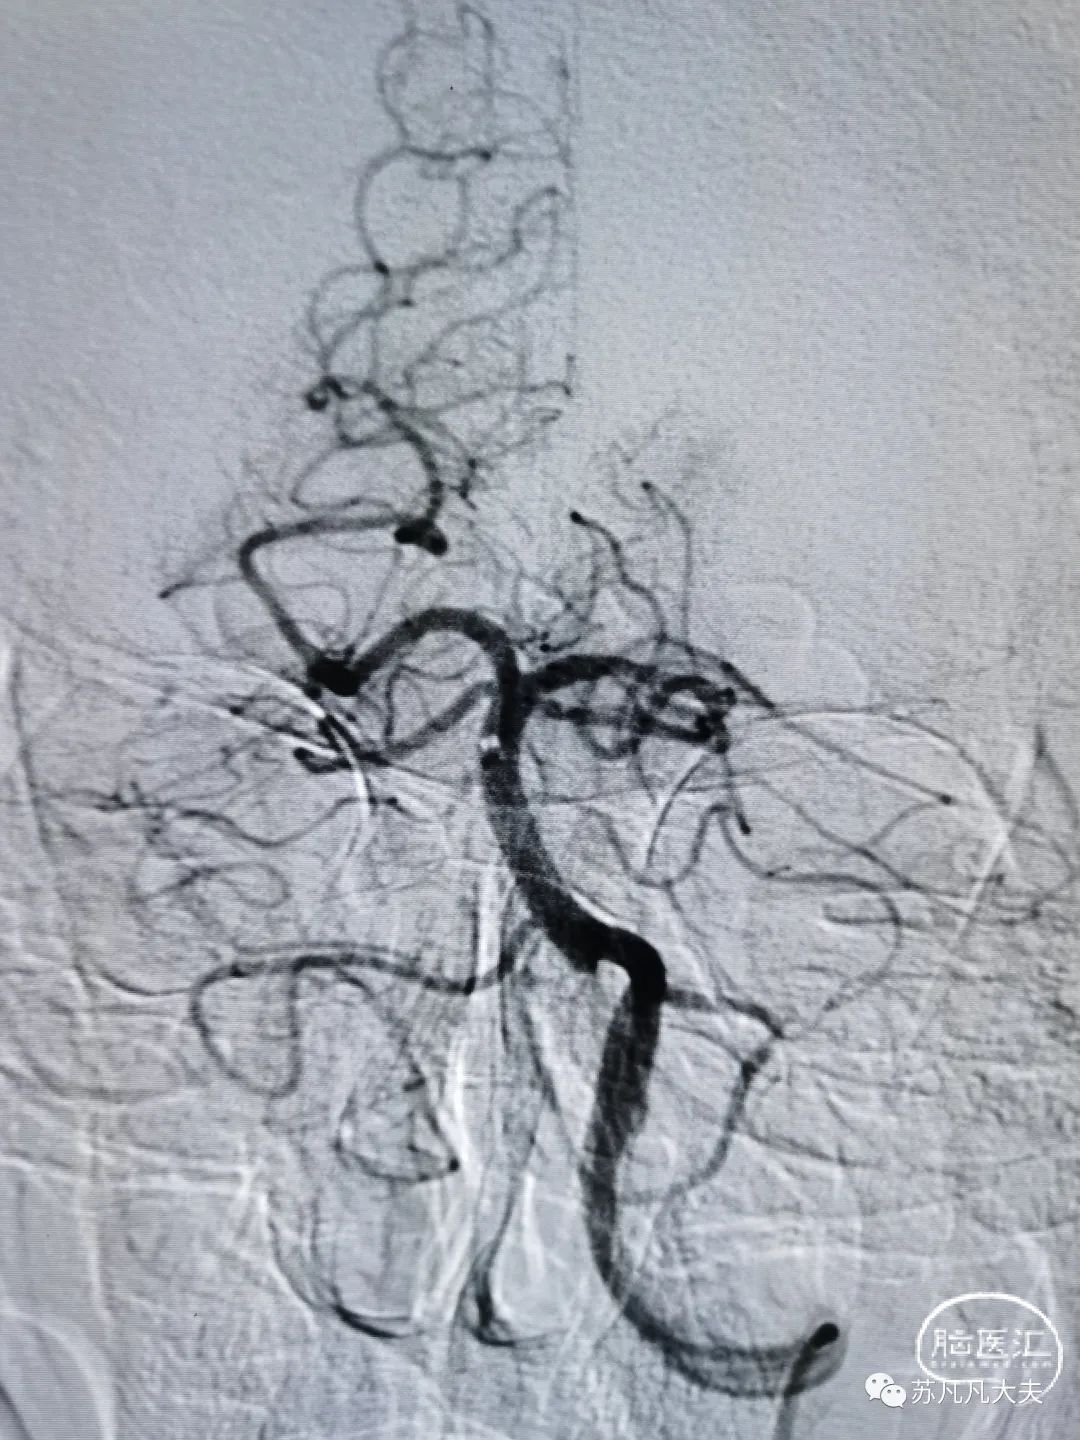

术后造影狭窄解除,颅内血供改善

术后给予静脉替罗非班,监测生命体征,患者意识水平较前明显改善,四肢活动良好。

次日复查头CT见梗死灶同核磁DWI显示病灶,左侧枕叶未见新发梗死灶。